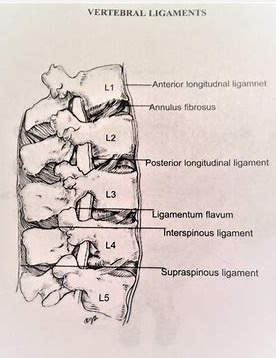

- ����������һ��һ�����������ģ������Ѿ�֪���˼�������һ���������Ĺ�ͷ������������С�������ɵ��ˡ���ô����ô���С��ͷ����ô������һ����أ�û�н�ˮ������ճ��һ�����Dz���ɢ���𣿵�Ȼ��������ȷʵ�����ý�ˮճ��һ��ģ�������һЩ�ṹ��������������һ���������˱Ƚ�ˮ��������ճ�����á���Щ�ṹ��Ҫ.....